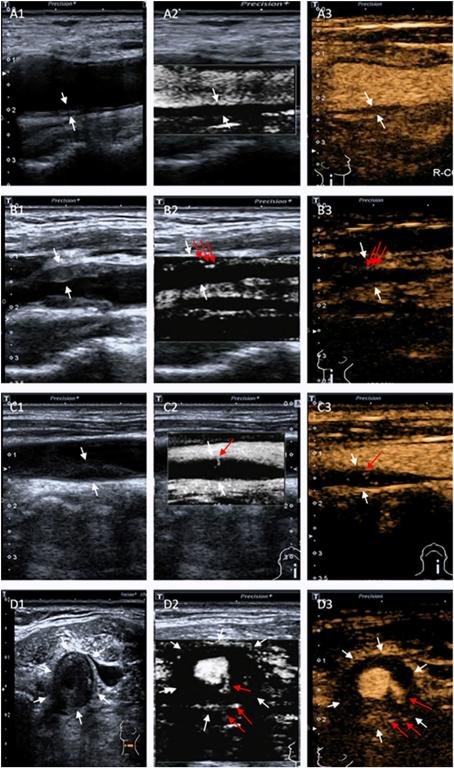

图1 常规超声����、SMI及超声造影分级

研究结果显示两名超声医师在应用SMI和CEUS方法诊断颈动脉斑块新生血管方面高度一致���。SMI与超声造影评价颈动脉斑块的新生血管分级结果一致���。SMI和CEUS分级与斑块厚度呈正相关��。研究表明CEUS和SMI对评估斑块的新生血管有很高的诊断价值���。